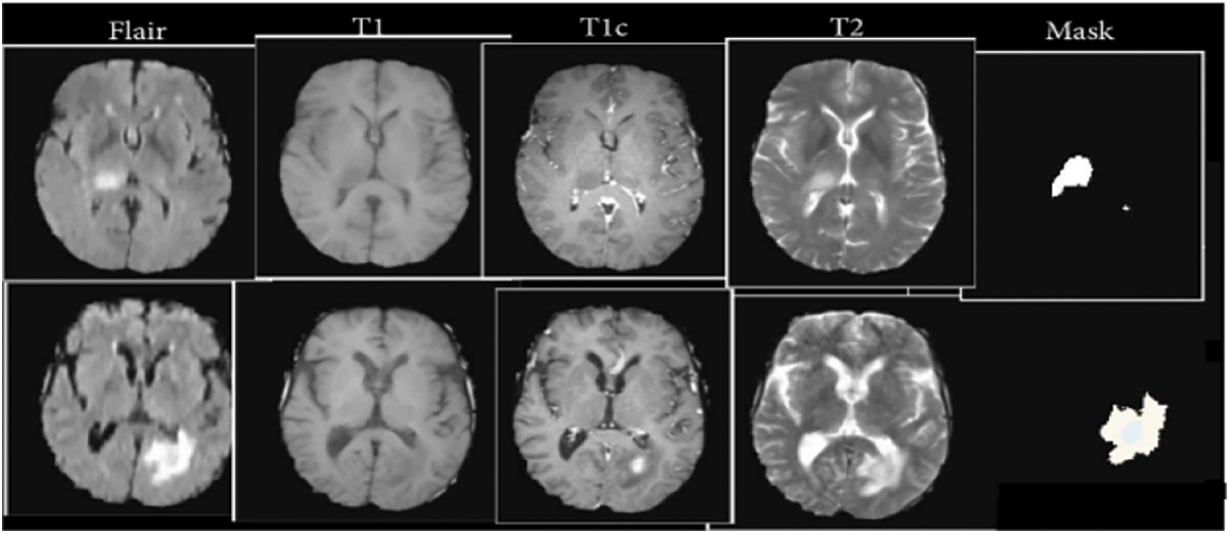

The BraTS 2020 dataset was used to determine how well our patterns performed. The images from 369 occurrences, including 293 HGG and 76 LGG, were included in the training set. MRI images from 66 occurrences of brain tumors with an undetermined grade were included in the affirmation set. It was a pre-built set created using the BraTS assignment organizers. The test set included images of 191 people who had brain tumors, 77 of whom had an operation known as a “gross total resection” (GTR) resection procedure and was expected to survive vaticination. The dataset split ratios are approximately (60:30:10). Table 1 represents the dataset details and split sizes.

We employed intensity normalization to lessen imaging inequality because the cost of MRI intensity varies depending on the imaging procedure and scanner used. Furthermore, the suggested reduction and the same old division of the tumor position are used to divide each MRI’s intensity value. We induced arbitrary reversing and arbitrary Gaussian clatter to compound the educational objective of reducing over-fitting. The data-preprocessed images from the four modalities are also standardized using the “Z-score method and the combined standardized images are then fed into the model. The Z-score is equal to the image falls below the mean when the standard deviation is divided by it.” Its precise formula which is represented in Eq. (1).